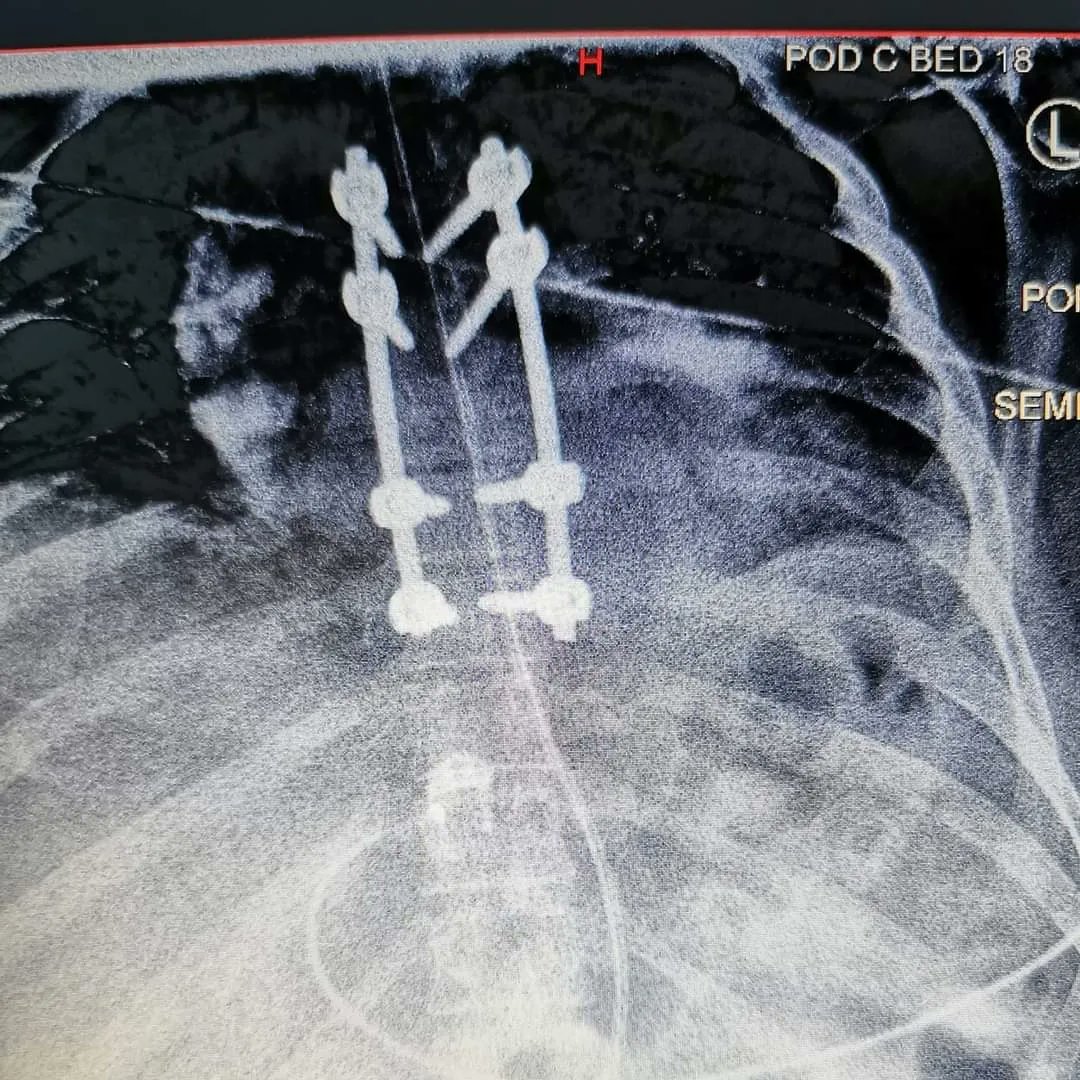

But after a serious brain injury, multiple fractures, spinal surgery, I'm still here and trying to fight fit against all the odds!!

@SCOMajorTrauma @ncaspines